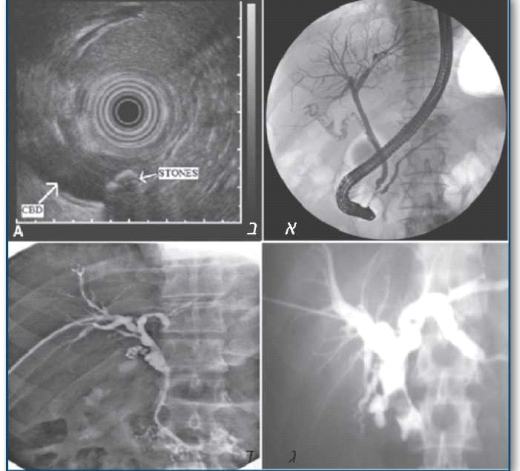

שקיפה רטרוגרדית של דרכי המרה והלבלב (ERCP)

בבדיקה זו נעשה שימוש במשקף מעי (Duodenoscope) שבו העדשה האופטית ממוקמת בצד קצה המכשיר, דבר המאפשר הסתכלות נכוחה וישירה של האמפולה. צנתור הפפילה מתבצע באמצעות צנתר המוחדר דרך תעלת העבודה של המכשיר, ודרכו מוזרק חומר ניגוד המדגים את צינורות המרה והלבלב. פרט לבדיקה אפשר לבצע פעולות טיפוליות כגון חיתוך השוער (Sphincterotomy), הוצאת אבנים, הרחבת היצרויות, החדרת תותב או נטילת דגימת רקמה. בעבר נחשבה בדיקה זו ל- "מתכונת הזהב" (Gold standard) של הדמיית דרכי המרה והלבלב, בעיקר כאשר מתוכננת גם התערבות טיפולית. באמצעות ERCP אפשר להדגים היטב את גורם החסימה המרתית.

- אבנים בצינור המרה: פריי (Frei) ועמיתיו דיווחו על רגישות בשיעור של 90% וסגוליות של 96% באבחון אבנים בדרכי המרה באמצעות ERCP. פעולות טיפוליות כגון חיתוך השוער וניקוי האבנים באמצעות העברת בלון או שליפתן באמצעות סלסלה, נמצאו יעילות ב- 85-90% מהמקרים. ריסוק מכאני של האבנים נמצא יעיל באותם מקרים בהם לא ניתן היה להוציא את אבני צינור המרה בשיטות השגרתיות, והעלה את שיעור ההצלחה ליותר מ- 90%. החדרת תותב על מנת לאפשר ניקוז טוב של דרכי המרה שמורה למקרים של אבני צינור מרה בסיכון מוגבר.

- גידולי לבלב ומרה: ERCP יעיל גם באבחון גידולים של הלבלב ודרכי המרה, אולם אבחנה סופית דורשת דגימה היסטולוגית מהממצא החשוד כדי לתכנן מדיניות טיפולית מתאימה: ניתוח, החדרת תותב, הקרנות או כימותרפיה. השיטות המקובלות לנטילת דגימות בבדיקת ERCP, הכוללות הברשה לשם בדיקה ציטולוגית (Cytology brush), דיקור מחטי עדין (FNA ,Fine-Needle Aspiration) שקיפתי או נטילת דגימה באמצעות מלקחי ביופסיה, מדגימות רגישות נמוכה-בינונית (20-60%), אך סגוליות המגיעה לכמעט 100%. ניתן להעלות את שיעורי הרגישות בביצוע שתי שיטות אבחון או יותר.

כולנגיוגרפיה מלעורית דרך הכבד (PTC)

בדיקה זו מבוצעת לרוב על ידי רדיולוגים. מבוצע דיקור של הכבד בהנחיה פלואורוסקופית (Fluoroscopy), שמטרתו כניסה לאחד מצינורות המרה התוך-כבדיים שמעל לצינור המרה המשותף (CBD ,Common Bile Duct). חומר ניגוד מוזרק לתוך צינור המרה לשם הדגמת מקור החסימה.

הדגמה מוצלחת של צינורות המרה מושגת בכ- 100% מהמקרים עם הרחבת צינורות המרה, ובכ- 60-80% מהמקרים ללא הרחבה שכזאת. הבדיקה יעילה מאוד באבחון מקור החסימה ורמתה, ומסוגלת להבדיל בצורה טובה בין חסימה שפירה לחסימה הנובעת מממאירות. כמו כן, משמשת הבדיקה גם כטיפול לצורך ניקוז דרכי המרה.